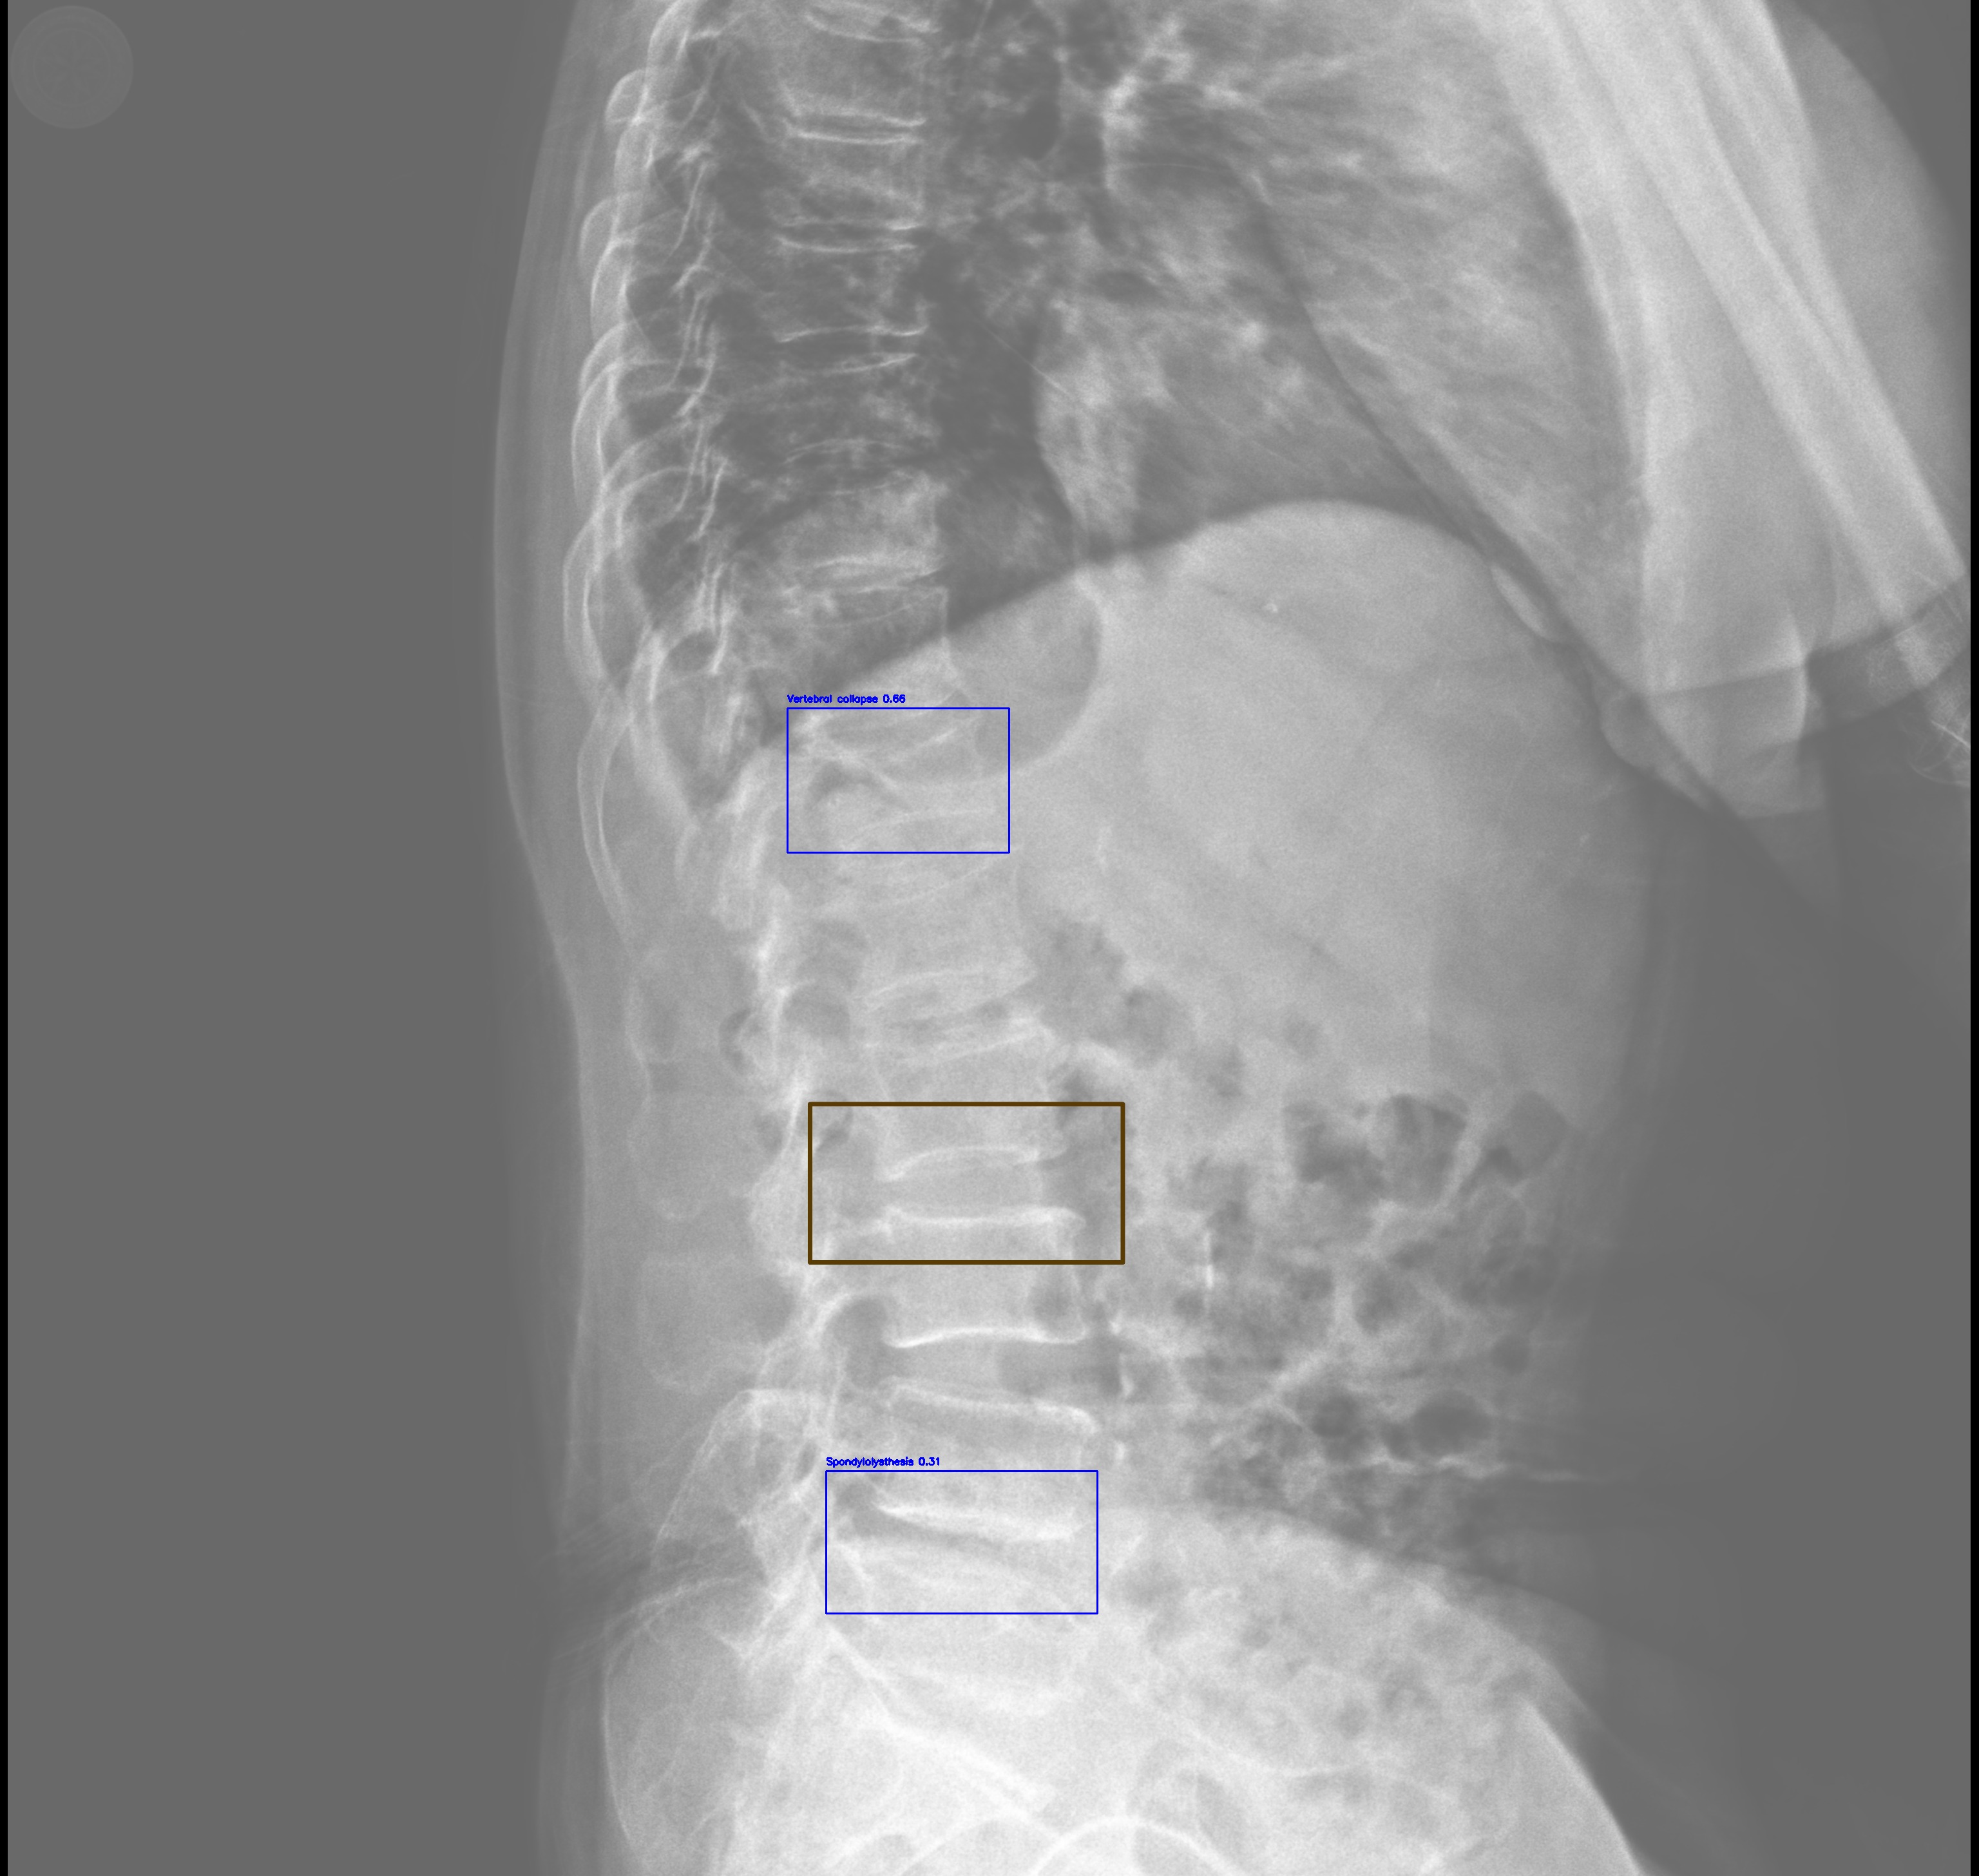

Automated Lesion Detection and Localization: Visual demonstration of the cascaded DERNet-YOLO11 framework on VinDr-SpineXR benchmark images. The figure presents eight representative cases including seven pathological conditions with precise bounding-box localization: (a) Vertebral Collapse, (b) Osteophytes, (c) Spondylolisthesis, (d) Surgical Implants, (e) Disc Space Narrowing, (f) Foraminal Stenosis, (g) Other Lesions, alongside (h) a Normal spine radiograph for comparison. Each pathological case demonstrates the model's capability to accurately detect and spatially localize subtle lesions despite significant class imbalance (46.9:1 ratio), small object scales (often <1% of image area), and anatomical structure overlap. The localization boxes validate the clinical applicability of the integrated triage–localization pipeline.

Vertebral Collapse

(a) Vertebral Collapse

Spondylolisthesis

(c) Spondylolisthesis